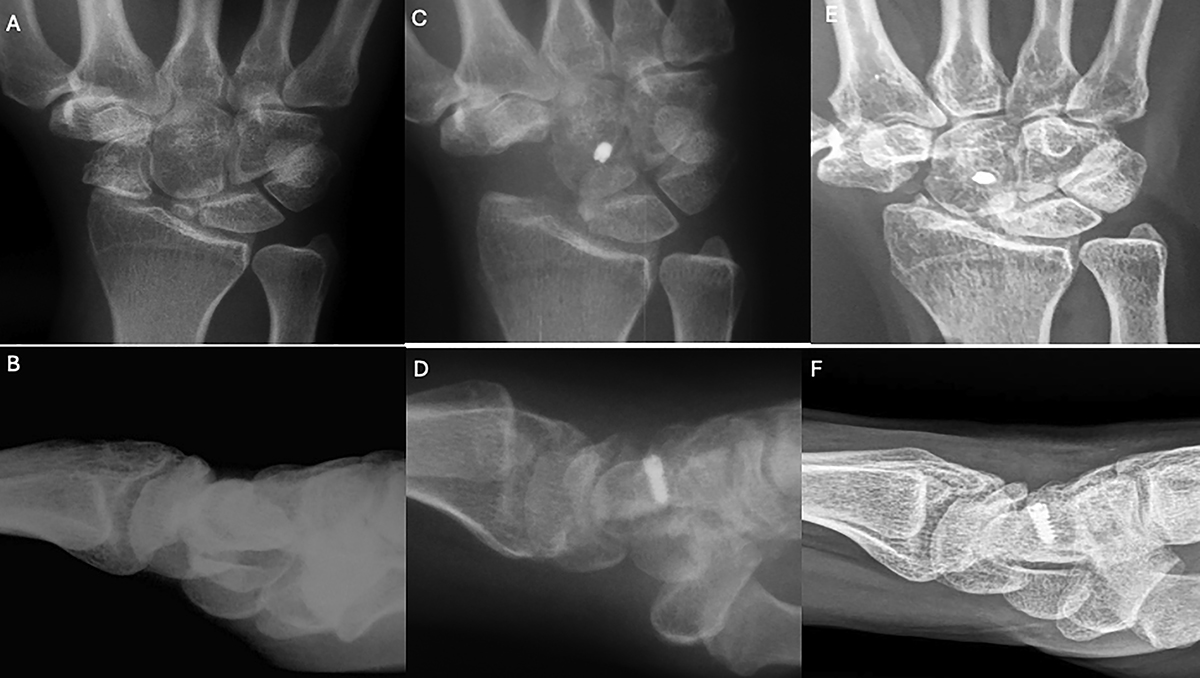

Clinical case of FCR tenodesis over capitate (Ligamentous grip) and Scaphoid excision. A and B. Preoperative wrist X-rays of SNAC stage II (AP and Lateral views). C and D. Postoperative wrist X-rays (AP and Lateral views) after the removal of K-wire (1month). E and F. Postoperative wrist X-rays (AP and Lateral views) after 12.25 years. Source: Dr. Emmanouil Apergis.